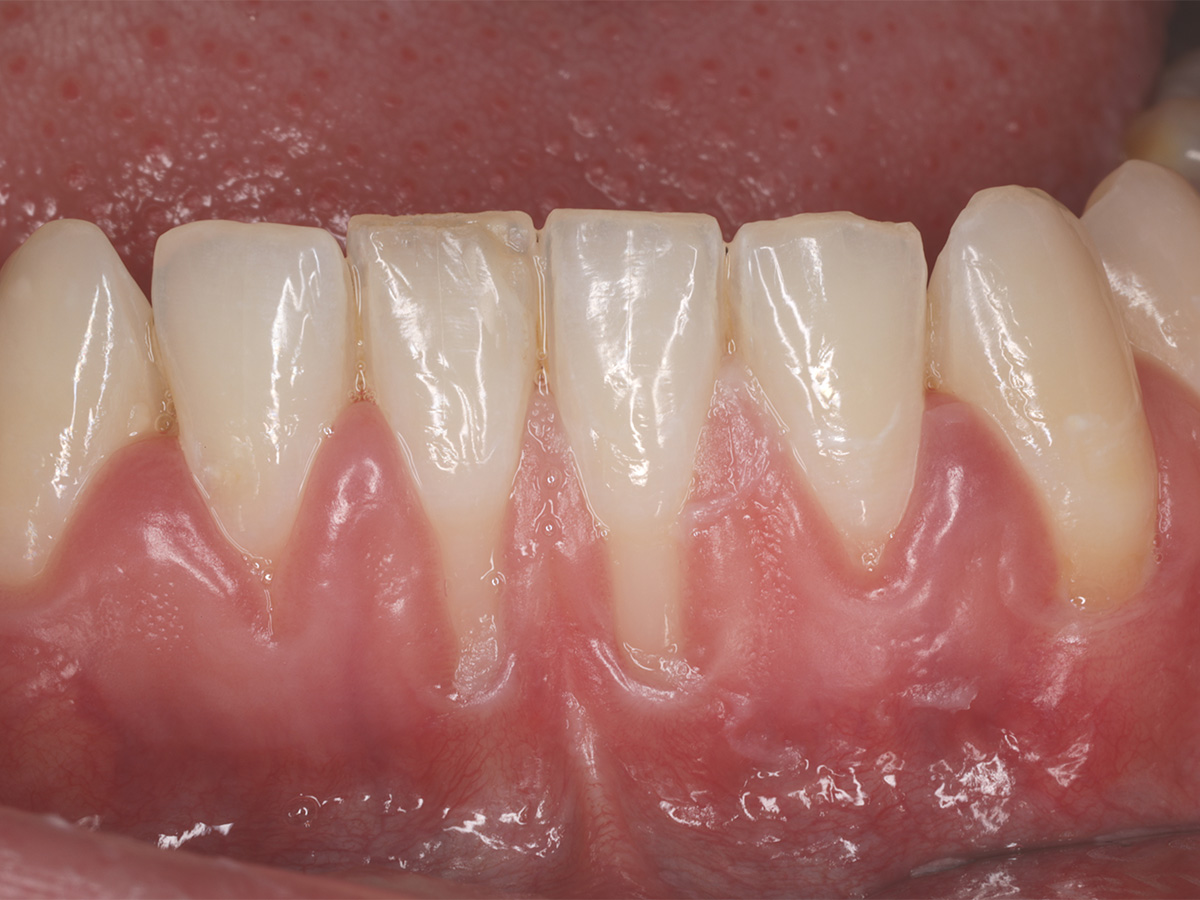

Die klinische Ausgangssituation zeigt in regio 31/41 Rezessionen des Typs 1 (RT 1) mit unzureichender Breite und Dicke an keratinisiertem Gewebe und einem flachen Vestibulum. Zur funktionellen Verbesserung der Weichgewebssituation in regio 31/41 erfolgte in diesem Bereich die Transplantation eines freien Schleimhauttransplantates (FST) aus der Gaumenregion. Zur Vorbereitung des Transplantatlagers erfolgte hierbei ausgehend von der mukogingivalen Grenzlinie die Präparation eines Spaltlappens nach apikal. Der präparierte Lappen wurde anschließend mit resorbierbarem Nahtmaterial apikal im Periost verankert. Die Transplantatentnahme erfolgte aus dem Gaumen, wobei auf eine gleichmäßige Transplantatdicke von ca. 1,5 mm geachtet wurde. Das Transplantat wurde auf der Empfängerstelle fest komprimiert und mittels Kreuznähten, die apikal des Transplantates im Periost verankert wurden, fixiert. Zusätzlich erfolgte eine Fixation an den Transplantatecken im koronalen Bereich mittels Einzelknopfnähten.

Abbildung 1

Klinische Ausgangssituation mit Rezessionen vom Typ 1 in regio 31/41 und unzureichender Breite und Dicke an keratinisiertem Gewebe.